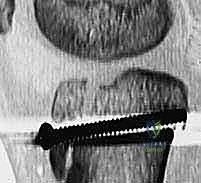

5. التثبيت الداخلي (Internal Fixation)

هنا تبرز مهارة الجراح في اختيار طريقة التثبيت التي لا تضر بصفيحة النمو (إذا كانت لا تزال مفتوحة).

* استخدام البراغي المجوفة (Cannulated Screws): يتم إدخال سلك توجيهي رفيع أولاً، وبعد التأكد من موقعه بالأشعة السينية داخل غرفة العمليات، يتم إدخال برغي أو برغيين من التيتانيوم القوي فوق السلك لتثبيت العظم. يحرص الدكتور هطيف على توجيه البراغي من الأمام إلى الخلف، وفي بعض الأحيان بزاوية مائلة لتجنب اختراق صفيحة النمو قدر الإمكان.